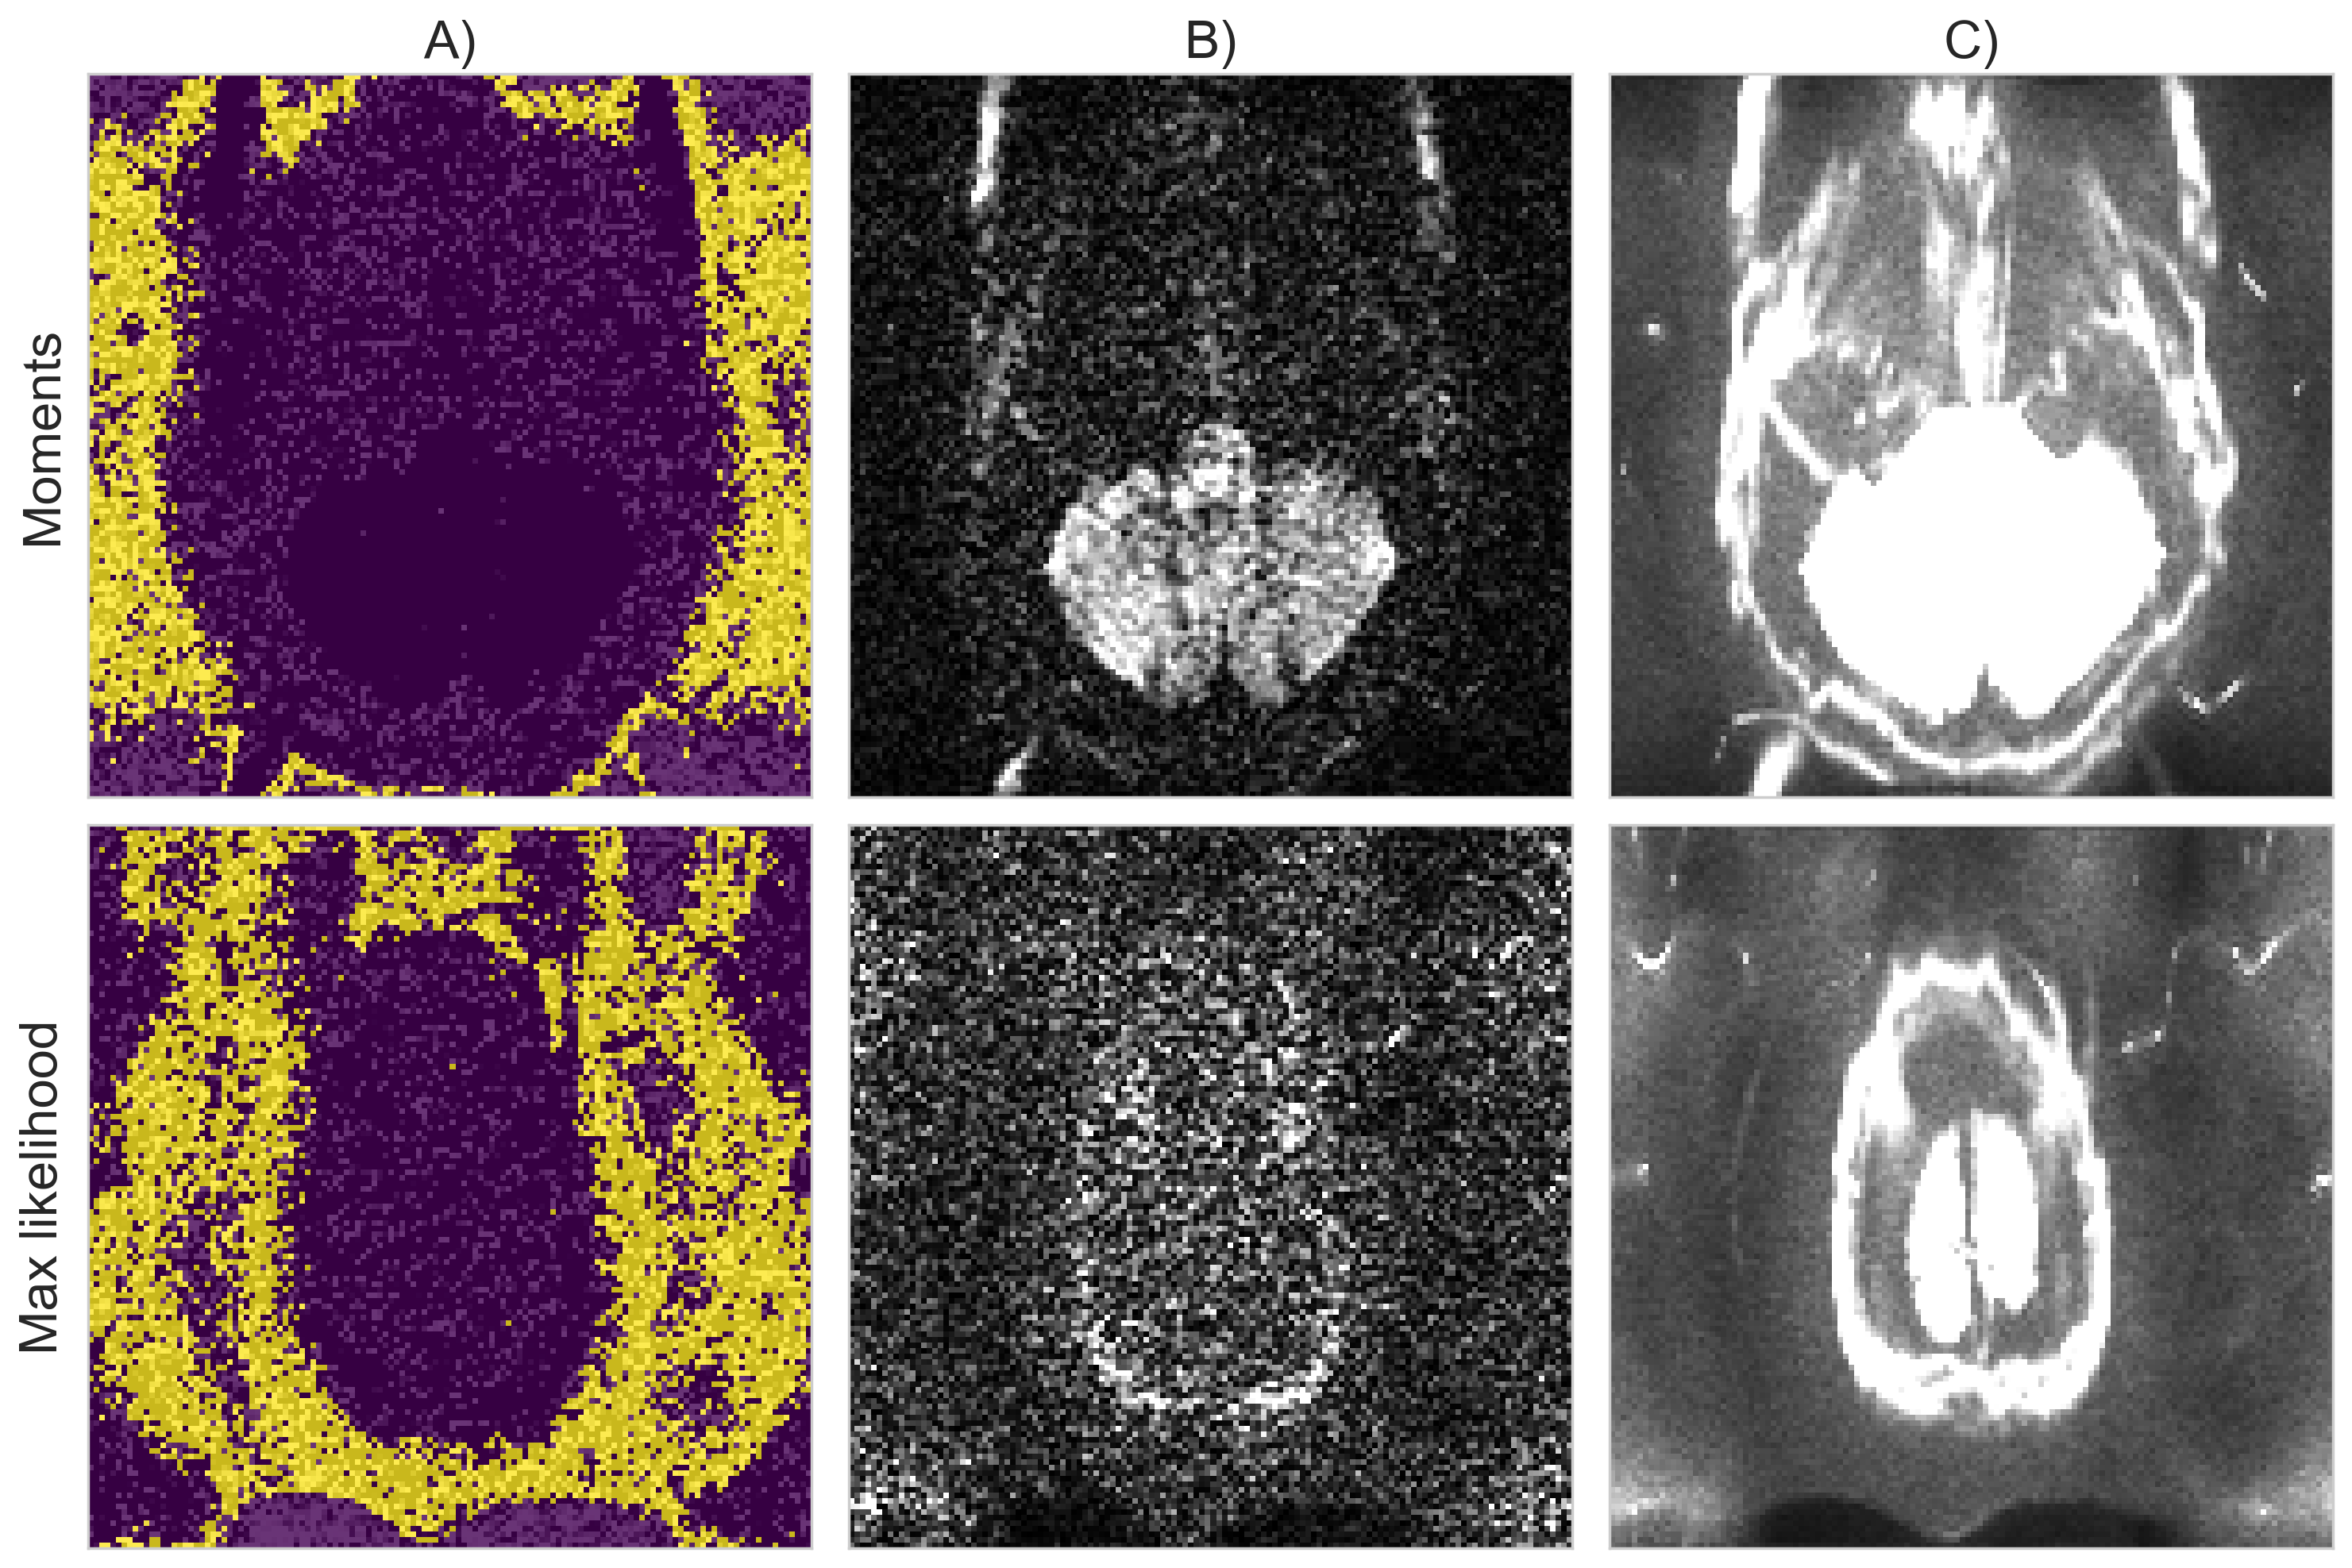

Fig. 9 shows an axial slice around the cerebellum and the top of the head which are corrupted by acquisition artifacts likely due to parallel imaging. Voxels containing artifacts were automatically discarded by both methods, preventing misestimation of and . The values computed from these voxels also offer a better qualitative fit than assuming a Rayleigh distribution or selecting non-brain data. We also timed each method to estimate on one of the GE datasets using a standard desktop computer with a 3.5 GHz Intel Xeon processor. The runtime to estimate (and ) was around 5 seconds for the maximum likelihood equations, 9 seconds for the moments equations, 11 seconds for PIESNO, 3 minutes for MPPCA and 18 minutes for LANE.

A)

B)

C)